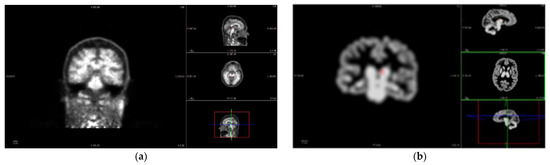

In the other imaging path, PET images are corrected to achieve a common spatial resolution of 8 mm to minimize inter-scanner differences [36]. Even if the methodology is general and several methods could be considered, this work employs three of them. The first method is the PVC2C approach [37,38], which is the most widely represented in the amyloid imaging literature. The second method is based on the calculation of the RSF [23,39], which has also been widely applied in PET image analysis. The third approach is based on not applying PVC to the PET study, as in the literature there is no consensus regarding whether PVC is necessary or not for quantitative PET analysis [10,13]. Figure 4 shows the differences that PVC methods introduce in the PET image studies.

Figure 4. PET images of the same patient as Figure 3. (a) PET image before applying Partial Volume Correction (PVC). In axial, sagittal, and coronal planes and 3D reconstruction, clockwise. (b) Result of applying Partial Volume Correction with Two-Components (PVC2C) to the PET study in (a), displaying the same planes in the same order.